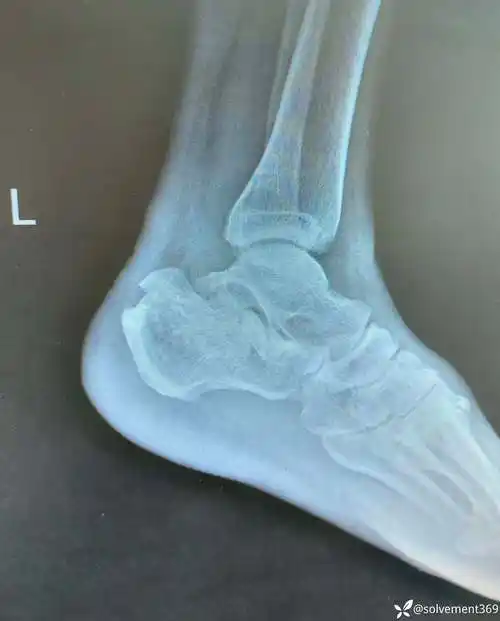

跟骨骨折差那么一点点